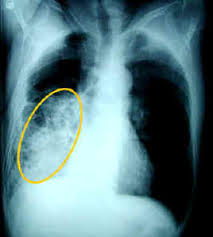

Η πνευμονία της κοινότητας παραμένει μία από τις πιο συχνές αιτίες θανάτου στις Ηνωμένες Πολιτείες της Αμερικής καθώς και σε όλο τον κόσμο. Αν και η διάγνωση της πνευμονίας γίνεται άμεσσα στις περισσότερες περιπτώσεις, υποκείμενα καρδιολογικά, αναπνευστικά προβλήματα υγείας όπως και η άτυπη εμφάνιση (χωρίς τυπική κλινική εικόνα) σε ηλικιωμένους ασθενείς μπορεί να καθυστερήσουν την αναγνώρισή της. Η τριάδα των συμπτωμάτων που δείχνουν ότι υπάρχει λοίμωξη (πυρετός ή ρίγος και αύξηση των λευκών αιμοσφαιρίων στην εξέταση αίματος), σημεία ή συμπτώματα ότι η λοίμωξη αυτή εντοπίζεται στους πνεύμονες (βήχας, παραγωγή πτυέλων, δυσκολία στην αναπνοή, πόνος στο θώρακα ή παθολογικά ευρήματα στην εξέταση από τον γιατρό) και η διαπίστωση ενός νέου διηθήματος στην ακτινογραφία θώρακος με ακρίβεια αναγνωρίζει έναν ασθενή με πνευμονία της κοινότητας. Οι ηλικιωμένοι ασθενείς μπορεί να μην έχουν την παραπάνω τυπική εικόνα ενώ η σύγχυση μπορεί να αποτελεί το μόνο σύμπτωμα τους με αποτέλεσμα να καθυστερεί η διάγνωση. Επίσης τα ευρήματα στην ακτινογραφία μπορεί να είναι ήπια: έτσι ένας μεμονωμένος ακτινολόγος μπορεί να μην αναγνωρίσει διηθήματα στην ακτινογραφία σε ποσοστό έως και 15% και 2 ακτινολόγοι μπορεί για την ίδια ακτινογραφία να διαφωνήσουν σε ποσοστό 10%. Με τον όρο "πνευμονία" εννοούμε λοίμωξη του πνευμόνων από ποικίλα παθογόνα αίτια. Ποικίλλει,δε, σε σοβαρότητα, από ήπια νόσο που μπορεί να αντιμετωπισθεί κατ´οίκον, ιδίως σε νεαρά άτομα, έως πολύ σοβαρή. Η πνευμονία αναφέρεται συχνά και ως ο " ξεχα-σμένος δολοφόνος". Ο Παγκόσμιος Οργανισμός Υγείας εκτιμά ότι αυτή η λοίμωξη του κατώτερου αναπνευστικού συστήματος αποτελεί την πιο συχνή αιτία θανάτου από λοιμώδες αίτιο παγκοσμίως και την τρίτη πιο συχνή αιτία θανάτου συνολικά με 3,5 εκατομμύρια θανάτους ετησίως. Η πνευμονία μαζί με τη γρίπη συνιστούν την ένατη πιο συχνή αιτία θανάτου στην Αμερική με τουλάχιστον 50 χιλιάδες θανάτους το 2010. Η πνευμονία της κοινότητας ή εξωνοσοκομειακή (δηλαδή σε όσους ζουν στα σπίτια τους και όχι σε ιδρύματα, γηροκομεία, νοσοκομεία, φυλακές κλπ) όταν είναι τόσο σοβαρή ώστε να χρειάζεται νοσηλεία σε νοσοκομείο σχετίζεται με αύξηση της θνητότητας, στα χρό-νια που ακολουθούν, για όσους επιβιώσουν από αυτήν. Αυτό ισχύει ακόμη και για νεαρούς ενήλικες χωρίς υποκείμενα προβλήματα υγείας. Το κόστος της σοβαρής πνευμονίας της κοινότητας που χρειάζεται εισαγωγή και νοσηλεία στο νοσοκομείο είναι πολύ υψηλό ειδικά αν χρειαστεί και νοσηλεία στη Μονάδα Εντατικής Θεραπείας. Παθογόνα αίτια Η αιτιολογία της πνευμονίας της κοινότητας δεν είναι συχνά εύκολο να καθορισθεί. Στο 25 έως 50% των περιπτώσεων δεν ανευ-ρίσκεται το παθογόνο αίτιο. Η γεωγραφική κατανομή, οι προηγηθείσες νοσηλείες σε νοσοκομεία, η πρόσφατη λήψη αντιβιοτικών για οποιοδήποτε λόγο, υποκείμενα προβλήματα υγείας (χρόνια πνευμονοπάθεια, βρογχεκτασίες, κάπνισμα, έκθεση σε πτηνά και ζώα, χρήση ενδοφλέβιων ουσιών, λοίμωξη με τον ιό του H.I.V., αλκοολισμός, η πιθανότητα εισρόφησης, η επιδημία γρίπης) μπορεί να διαφοροποιούν την αιτιολογία της πνευμονίας της κοινότητας. Αντίθετα, η εποχή αμφισβητείται αν έχει συμμετοχή στην αιτιολογία των πνευμονιών εκτός από τους ιούς που προκαλούν συνηθέστερα λοιμώξεις του αναπνευστικού το χειμώνα και την άνοιξη. Τα πιο συχνά αίτια αποτελούν: ο πνευμονιόκοκκος (streptococcus pneumoniae), ο αιμόφιλος της γρίπης (hemophilia influenza) και τα gram αρνητικά μικρόβια, οι άτυποι μικροοργανισμοί (χλαμύδια, μυκόπλασμα),η λεγιονέλλα ( legionella) και οι ιοί (ιοί της γρίπης και της παραγρίπης, αδενοϊός, κυτταρομεγαλοϊός). Οι παραπάνω μικροοργανισμοί θα φθάσουν στους πνεύμονες συνήθως με την εισπνοή μικρών εξαερωμένων σταγονιδίων. Πως διαγιγνώσκεται; Σε άτομα που δεν έχουν υποκείμενα καρδιοναναπνευστικά ή άλλα προβλήματα η διάγνωση είναι σχετικά εύκολη. -Τα συμπτώματα που συχνότερα παρουσιάζονται είναι: πυρετός με ρίγος, έντονη κόπωση, ανορεξία, βήχας, παραγωγή πτυέλων (τα πτύελα μπορεί να έχουν πρόσμιξη αίματοςδηλ.αιμόπτυση), δύσπνοια, πόνος στο θώρακα. Στη φυσική εξέταση ο ιατρός θα διαπιστώσει ταχυκαρδία, ακροαστικά ευρήματα από τους πνεύμονες ενώ σε πιο σοβαρές περιπτώσεις διαπιστώνεται χαμηλό οξυγόνο (μείωση του κορεσμού της αιμοσφαιρίνης με το οξύμετρο), πτώση αρτηριακής πίεσης και σε ηλικιωμένους ασθενείς σύγχυση και έκπτωση του επιπέδου συνείδησης. -Οι αιματολογικές εξετάσεις δείχνουν συνήθως αύξηση των λευκών αιμοσφαιρίων του αίματος, αύξηση των δεικτών φλεγμονής (Ταχύτητα Καθίζησης Ερυθρών και CRP) και πιθανόν αύξηση της ουρίας. -Η ακτινογραφία θώρακος (face+profil) θα δείξει πνευμονικά διηθήματα με ή χωρίς συλλογή πλευριτικού υγρού. Θεραπεία Με τη διάγνωση της πνευμονίας της κοινότητας από τον παθολόγο μας, εφόσον εκείνος κρίνει ότι μπορούμε να παραμείνουμε στο σπίτι και δεν είναι απαραίτητη η νοσηλεία στο νοσοκομείο, θα πρέπει να ξεκινήσει άμεσα η κατάλληλη αντιβιοτική ή αντιϊκή αγωγή (αναλόγως με το πιθανό ή εργαστηριακά επιβεβαιωμένο αίτιο) για 5 έως 7 ημέρες (εκτός αν υπάρχει αιτία μειωμένης άμυνας του οργανισμού, οπότε μπορεί να χρειαστεί πιο παρατεταμένη θεραπεία) και θα χρειάζεται συχνή παρακολούθηση και επανεξέταση μέχρι να επιβεβαιωθεί η ίαση. Μοιραστείτε το άρθρο